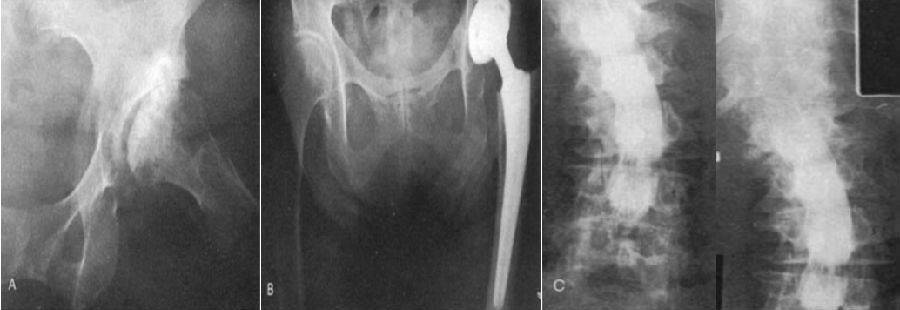

Case 1(湘雅二医院):

• 女,75岁,右THA 14年,左髋痛14年,腰背痛10年,无跛行和下肢症状

• 查体:- L4/5压叩痛

-左髋“4”字征(+),左股四头肌萎缩

• 手术:左THA(疼痛来源于髋)

• Case 2(湘雅二医院)

-王某某,男,79岁, 反复腰痛8年

- 8月前出现右侧髋外侧明显疼痛,活动受限,伴左侧臀部疼痛并放射至大腿、小腿外侧至足背

-既往史:冠心病, 糖尿病, 脑梗,尿毒症

-体查:脊柱S型侧弯,双下肢感觉减退,右髋关节“4”字征(+),左侧直腿抬高及加强试验(+)

-治疗:先做THA,术后3月左下肢症状加重,不能行走,行局麻下孔镜翻修